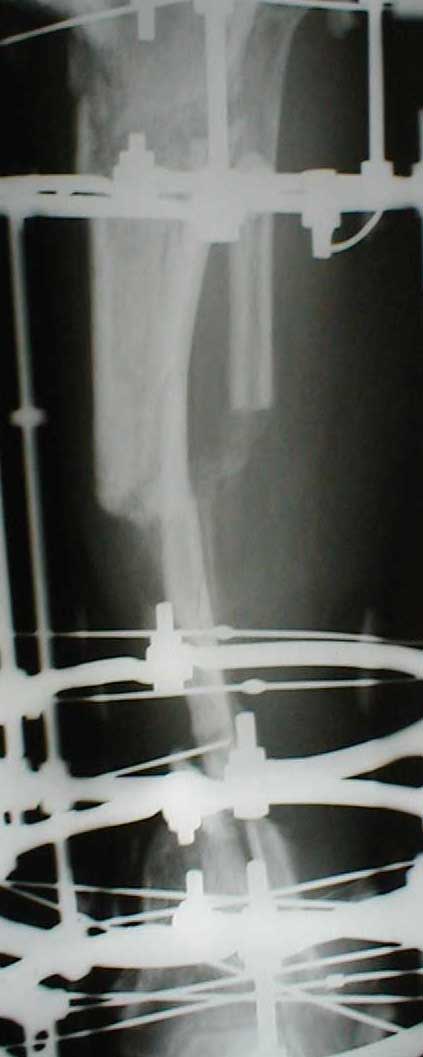

Zdes' snimky posle poslednego montazha apparata prilagaiutsa

Yours Castro

Кликните для загрузки файла IMG_0501.jpg

Может быть не совсем в тему, но... Скажите, а чем вызвана такая необычная компоновка аппарата: кольцевидный фиксатор и стержни? На первый взгляд так теряются преимущества монолатеральной стержневой фиксации (легкость перевязок) без достаточной компенсации достоинствами классического ВКДО Илизарова?

Андрей Крылов 02 Июнь 2005, 20:10

"Необычная" фиксация, предполагает осуществление максимальной стабильности проксимального фрагмента б\б кости. Как ее добиться - дело лечащего врача. При всем уважении к монолатеральным фиксаторам, лучше пожертвовать неудобствами при перевязках, чем нестабильностью фрагментов. Если поставлена цель сохранения конечности, то на данном этапе стабильность это - пункт № 1.

Ito vizvanno tem, chto, ja hotil dobitsa bistreshei stabilnoi fiksasii, chto bi dat' sosudestomu hirirgu vozmoznost' rabotat' po medialno-zadnoi poverhonoste, u menjia nibilo dostatochnoe vremjia, dla togo, chto bi provodit' spisy, ih natiagivat' i t.d. i t.p. pre itom ja ni narushal prinsepov vneshnei fikasii dla fixasii poddobnih perelomov. U manjia bili pod rukoi fixatory Hoffmana, i drugie unilateral fixatores, no ja ni stal imi polzovatsa, potomuchto, na moi vzglad', oni malo effectivnie dla dannogo vida povrezdenjia, t.k., oni sozdaiot bol'shoi richag, v rezultate- ita vliaet na stabil'nost', ossobenno v distalnih otdelah, ito kak pravilo, prevodit' k zametnomu oteku nize pereloma, a tut mi smogli provodit'sterzny v teh ploskostiah, kororie nam udobnie v udobnih mestah sobludjia prinsepov "bistro, stabilno, minimalno"

Malo togo, Unilateral frames, ni sposobnie k dalnishemu razvetio, i rano ili pozdno predetsa perehodit' na Ring fixators, tak, chto luche iz nih i nachinat', a voprochem, u kazdego vracha est' vsai vzglady i biomechanicheskie soobrazenjia na opredelennio temu, u opredellnogo bolnogo, i ni vazno kakogo sveta koshky, i vazno chto ona lovit' mish'.